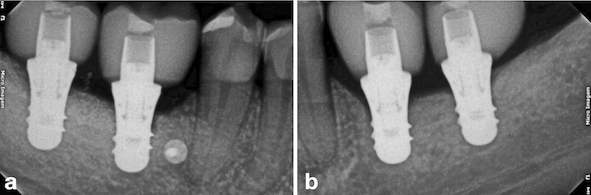

After two months from the placement of the implants in the region of teeth #46 and #47 (Fig. 9a), the free gingival graft was removed from the palatal region of teeth 23# and 27# (Fig. 9b). The grafts were fixed by crossed horizontal sling suture and interrupted sutures with 5-0 Nylon wire (Ethicon®, Jonhson& Johnson, São José dos Campos, São Paulo - Brazil) (Fig. 9c). Screw-retained lithium disilicate single ceramic crowns were manufactured after three months (Fig. 9d) by using the CEREC CAD-CAM system, and it was cemented onto a Variobase-C® (Straumann, Basel, Switzerland) abutment with a final torque of 35 N.cm (Figs. 10 and 11). After a 3-years follow-up, bone loss around the implants or presence of gingival inflammation was not observed, and the prosthesis adaptation was found to have no alteration either (Fig. 12). Therefore, aesthetics, as well as masticatory and speech functions were preserved.